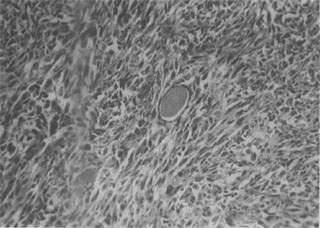

1.纤维肉瘤(fibrosarcoma) 是肉瘤中常见的一种,其发生部位与纤维瘤相似,以四肢皮下组织为多见。分化好的纤维肉瘤细胞多呈梭形,异型性小,与纤维瘤有些相似;分化差的纤维肉瘤则有明显的异型性(图7-17)。纤维肉瘤分化好者生长慢,转移及复发较少见;分化差者生长快,易发生转移,切除后易复发。

图7-17 纤维肉瘤

瘤细胞呈梭形,体积较大,核大,核分裂像较多,具明显的异型性